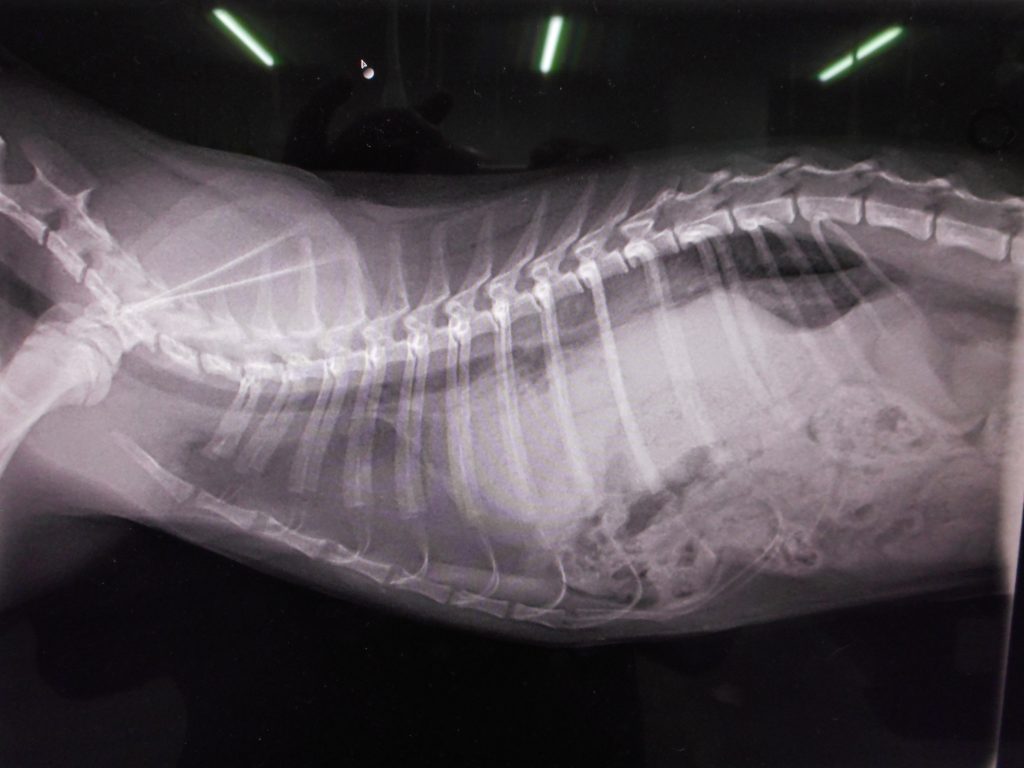

この病気、かなり深刻です

横隔膜に穴が開いています

診断:横隔膜ヘルニア

自宅では、次第に呼吸困難になってきたそうです

開口呼吸が目立ってきた・・・

手術が必要そうですが、危険な手術となります